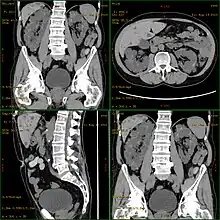

![]() | |

| Severely affected polycystic kidneys removed at time of transplantation | |